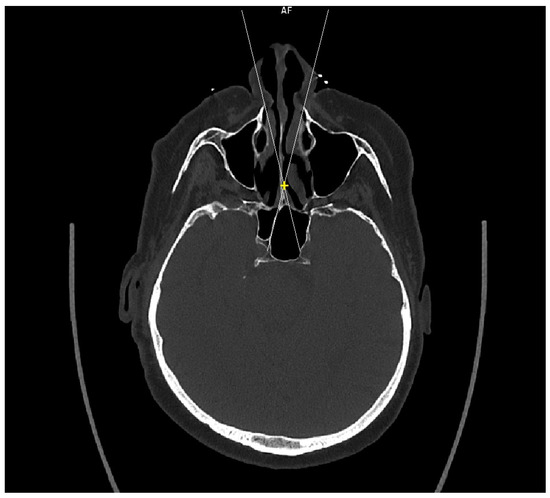

Cadaver CT scan: Two cadaver heads were used for the CT scan measurement. The CT scans were performed on a Siemens Somatom force scanner (Siemens healthineers, Praha, Czech Republic). With each cadaver head, a different size of septal resection was simulated in SyngoVia software (VB40, Siemens healthineers, Praha, Czech Republic). For the simulation, we used HrCT images with a slice thickness of 0.6 mm in a semi-axial view. A virtual 1 cm posterior part septal resection was performed by marking a yellow cross on the nasal septum 1 cm from the anterior sphenoid wall. A white line was drawn to simulate the insertion of a straight instrument. The defined points for this line were the bony lateral part of the nasal aperture and the marked yellow cross on the nasal septum. The place where this ongoing white line crossed the posterior bony edge of the sphenoidal sinus represented the most lateral point that could be reached in the sphenoid sinus with a straight instrument without infracturing the nasal septum. This point was then marked with a yellow star. The same procedure was performed for both nostrils. The same principle and procedure were used for a 2 cm resection simulation with the second cadaver head (Figure 3).

Figure 3. CT scan, semi-axial view, 1 cm distance from anterior sphenoid wall on nasal septum (yellow cross), virtual straight instruments inserted into sphenoid sinus simulating binostril approach (white lines), most lateral area in sphenoid cavity that can be reached with straight instrument with 1 cm septal resection without infracturing the nasal septum (yellow stars).